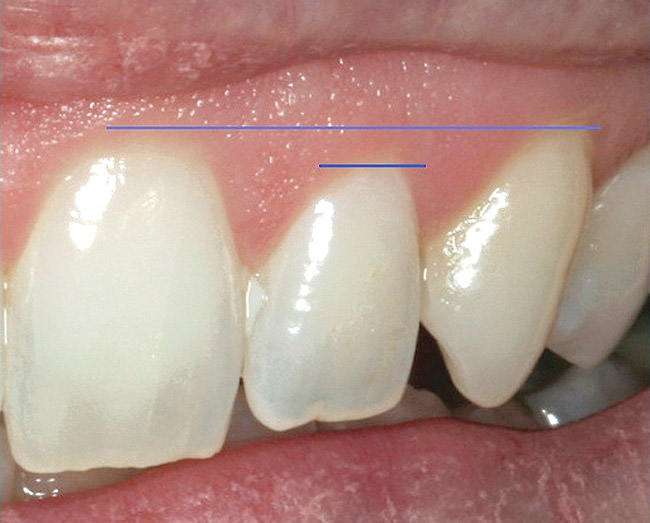

Will the removal or retention of the tooth allow gingival symmetry? Gingival symmetry is defined as an imaginary line that should be collinear, connecting the central incisors and canines and parallel with the interpupillary line or horizon if the interpupillary line is canted. Ideally, this line should also be parallel to the incisal edge and the curvature of the lower lip.37 The gingival margin of the lateral incisor should be even with or coronal to this line by a maximum of 3 mm (Figure 16).38 If these parameters are not met, then orthodontic or periodontal procedures or both will need to be performed to place the tooth in the correct esthetic position.